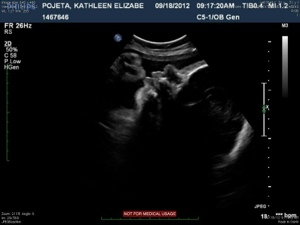

The next four images just show various views of the strands/septations that are visible within the sac.

20120921-213531.jpg